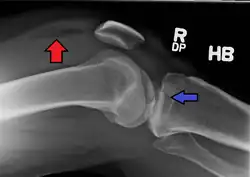

Lipohemarthrosis (presence of fat and blood from bone marrow in the joint space after an intraarticular fracture) seen on X-ray in a person with a subtle tibial plateau fracture -

Lipohemarthrosis due to a tibial plateau fracture -